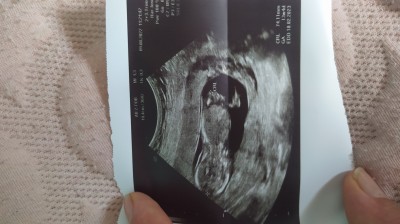

Arkadaşlar ben 14 haftalık hamileyim bgn özele gittim ikili tarama testi yapayım dedim doktora cinsiyetini sordum net değil dedi size tahmin de bulunmanızı istiom sizce cinsiyet erkek mi kız mı sadece merak ettiğim için tahminlerinizi almak istedim bende biliom sizin cinsiyet hakkında bilgi sahibi olmadığınızı

Gebelik haftası 14

Burda bebisin sirti dönük bnce :D